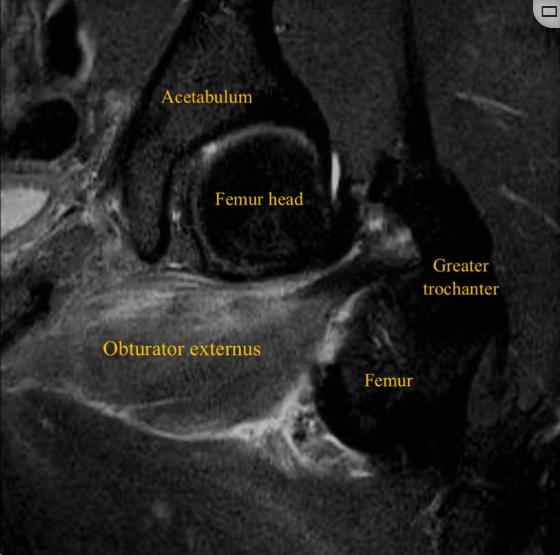

患者男性,32岁,职业足球运动员,在赛季训练期间出现急性左腹股沟疼痛和臀部疼痛,视觉模拟量表(VAS)评分为8/10,这是由髋关节的快速和负重内旋运动引起的,髋关节和膝关节弯曲约90度,在快速改变方向和切入进攻的过程中,功能立即丧失。患者否认腿部有任何麻木、虚弱或辐射性疼痛。体检时,没有瘀伤、瘀斑、水肿或肿胀。坐骨结节触诊有轻微疼痛和压痛。在内收肌、腘绳肌或髂腰肌的特定测试中未发现异常。膝关节和髋关节处于90°时髋关节主动外旋和被动内旋都会引起髋关节疼痛。这位运动员跛行。对左髋关节进行x线检查,以排除髋关节病变,包括股骨髋臼撞击。核磁共振成像显示左侧闭孔外肌的后腱膜下/肌腱膜撕裂,从耻骨起点延伸至外侧肌腱连接处,横断面测量为10 cm,前后径为3.5 cm,伴有股方肌和闭孔内肌间质水肿(图1-4)。

图2、左大腿斜冠状面(STIR) MRI显示左闭孔外撕裂